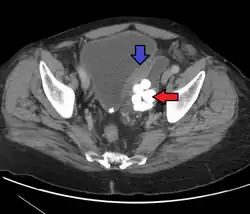

Bladder diverticula containing stones. The bladder wall is thickened due to possible transitional cell carcinoma.